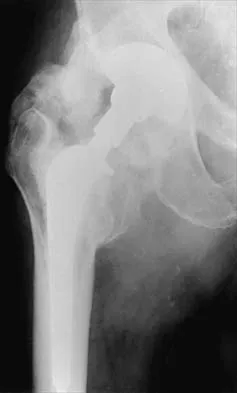

Orthopedic MCQs

Test your knowledge with updated Orthopedic MCQs for 2026. Perfect for board exam preparation, FRCS, and Prometric test practice.